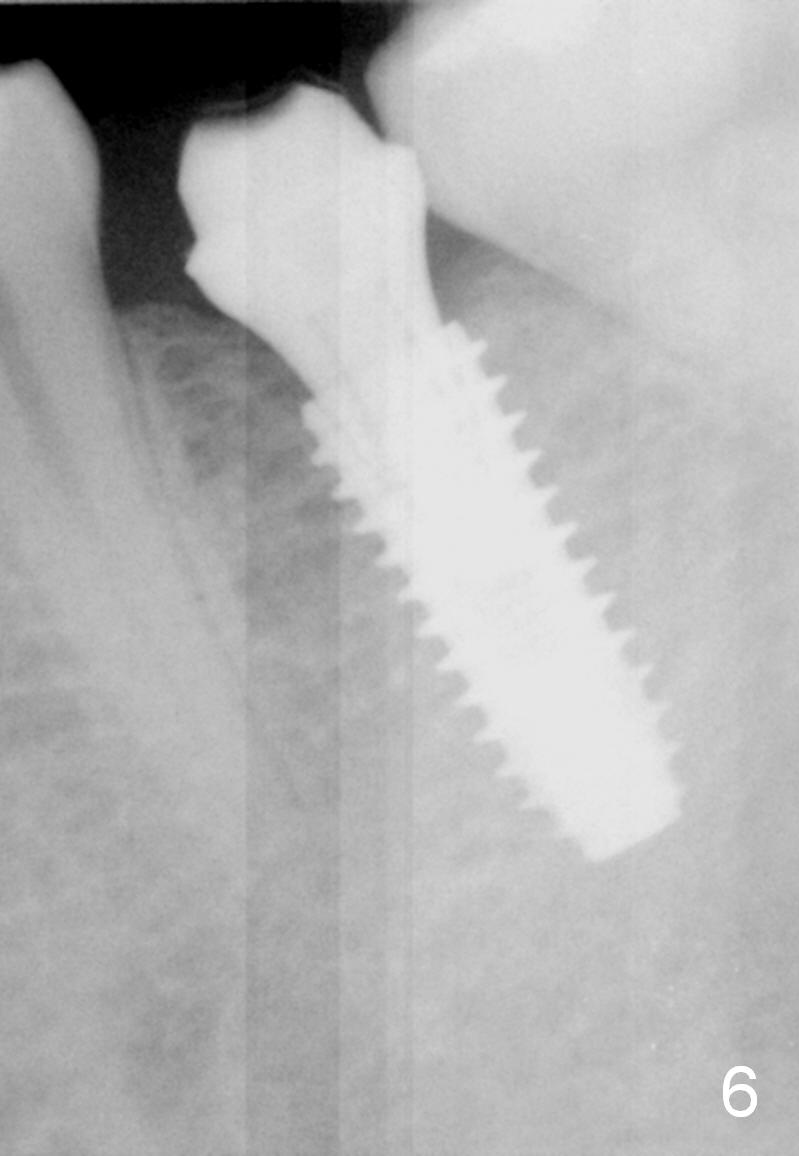

A 31-year-old woman agrees to have implant at #19 (Fig.1) after redoing MOL composite at #20 (Fig.2 *). The edentulous mesiodistal space is narrow (~ 6 mm in Fig.3). If the buccolingual bone width is found to be good after incision, a large implant is preferred. To gain space mesiodistally, the proximal surfaces of the neighboring teeth will be reduced (Fig.2 blue curved lines).

There is no bone loss 3 months postop (Fig.6).